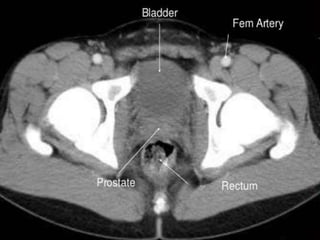

CT cross sectional anatomy.